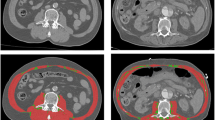

Assessment of conventional CT body composition parameters

For each patient, a transverse CT image at the mid-height of L3 was exported from the radiological Picture Archiving and Communication system (PACS, GE Centricity, Milwaukee, USA). For further processing, the open-source software Image J (National Institutes of Health) was used in line with a step-by-step guide previously published by Gomez-Perez et al [23]. Figure 1 shows these post-processing steps in an exemplary study patient. First, the circumference of the inner and outer abdominal and paraspinal musculature, as well as the circumference of L3 was outlined. After application of a muscle-specific threshold (−29 to +150 Hounsfield units [HU]), the area within the inner perimeter of the musculature (Fig. 1B) and of the vertebra (Fig. 1C) were subtracted from the area within the outer perimeter of the musculature (Fig. 1A). The derived skeletal muscle area was divided by square body height (m) to provide the SMI (cm2/m2). The MRA (HU) was given by the mean density of the whole abdominal muscle area (Fig. 1F). The waist circumference (WC, cm) was assessed by contouring the body circumference at the height of L3. The subcutaneous adipose tissue area (SAT, cm2) was calculated by subtracting the area within the outer muscle circumference (Fig. 1D) from the whole-body area after application of a fat-specific threshold (−150 to −30 HU). The visceral adipose tissue area (VAT, cm2) was derived from the area within the inner muscle perimeter (Fig. 1E) using the same fat-specific threshold.

Postprocessing contours to quantify conventional CT body composition parameters. Displayed is the outer (A) and inner (B) perimeter of the abdominal and paraspinal muscle, and of the third lumbar vertebra (C), as well as the whole abdominal muscle area (F) each with the muscle-specific threshold of –29 to +150 HU. With a fat-specific threshold of −150 to −30 HU, (D) displays the outer and (E) the inner muscle perimeter. The skeletal muscle index is then given according to Gomez-Perez et al [23] by subtracting B and C from A. The muscle radiodensity attenuation is given by F. The subcutaneous adipose tissue is given by the area outside the defined muscle perimeter in D, and the visceral fat by the area within the perimeter in E